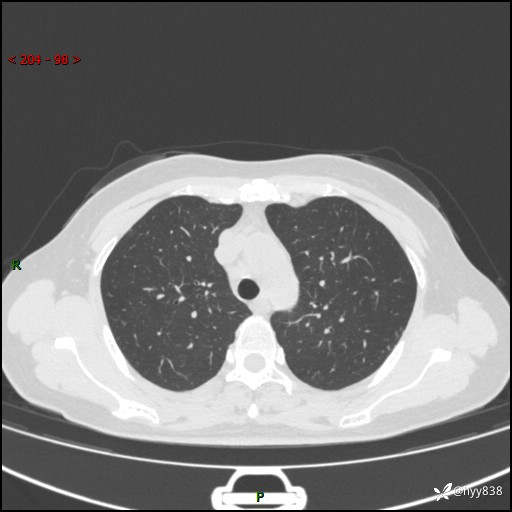

【患者信息】:58岁/女

【主诉】:体检发现肺结节

【检查】:胸部CT平扫+增强